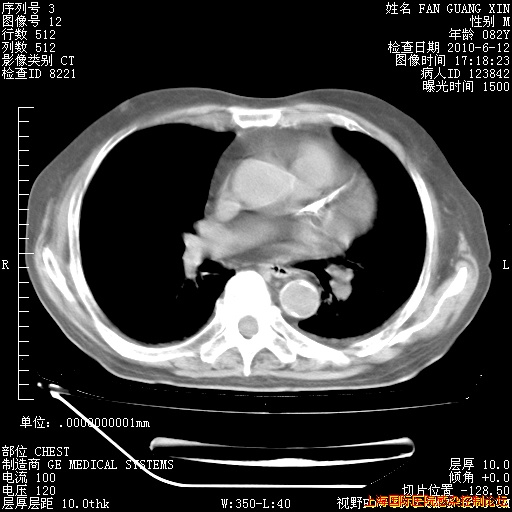

补发6月12日肺部CT肺窗

6月12日肺窗

6月12日纵膈窗

整整相隔30天的肺部CT好像有所好转啊。甲强龙减量第3天,需要观察体温。

海管,自昨日你和我通完话后,不知您岳父消化道症状有无缓解?体温怎样?阅读7.12日胸部ct,个人认为目前激素治疗是有效的,甲强龙减量是适宜的。因在抗痨治疗,需密切观察肝功、肾功能和血常规。不过,老年、长期住院和大量使用激素,很担心菌群失调发生